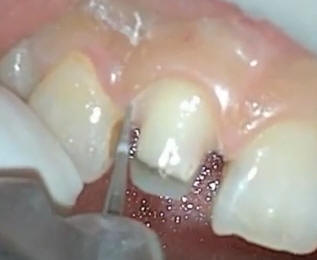

Reducción del borde

incisal |

Dejar suficiente espació

para la porcelana por lo menos 2 mm o más |

Ver el hombro realizado

en palatino que debe ser supragingival |